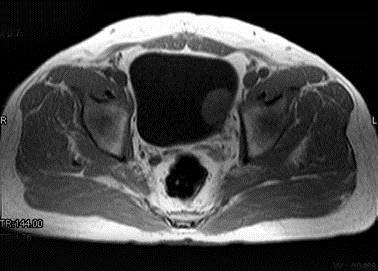

问题 男,59岁。血尿1个月。MRI检查如图所示。最可能的诊断是 ( )

选项 A、膀胱息肉 B、输尿管囊肿 C、膀胱癌 D、膀胱结石 E、膀胱内血块

答案 C